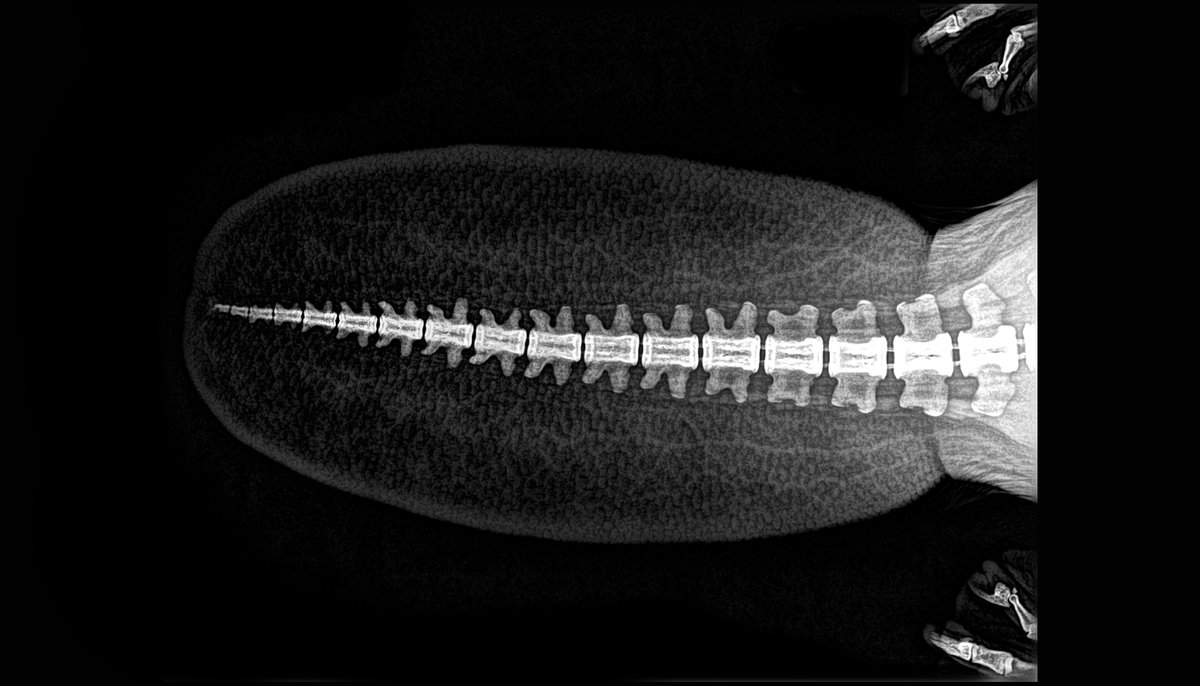

Tortuga